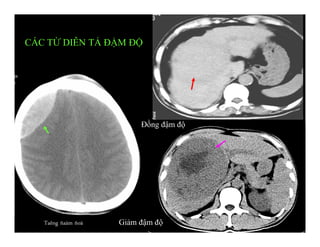

CÁC TỪ DIỄN TẢ ĐẬM ĐỘ

Giảm đậm độ (Hypodense)

Đồng đậm độ (Isodense)

Tăng đậm độ (Hyperdense).